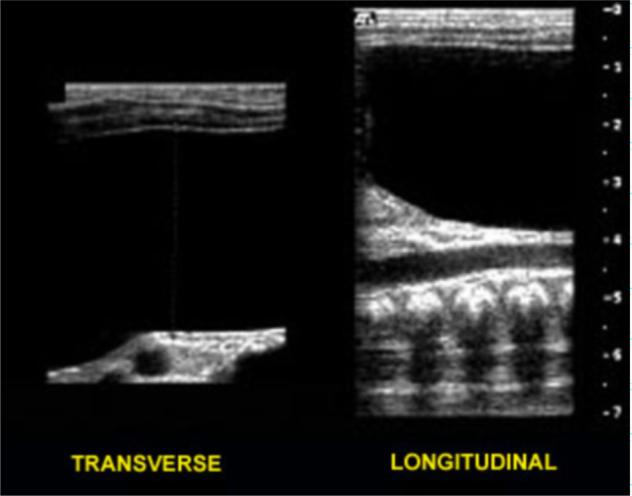

We report a case of megacystis-microcolon-intestinal hypoperistalsis syndrome (MMIHS) in a newborn female infant who presented with an abdominal mass, absent bowel sounds, and feeding intolerance with bilious emesis. MMIHS is a rare congenital bowel and bladder defect requiring surgery and chronic total parenteral nutrition in an attempt to sustain life. With few exceptions, it is predominately fatal within the first six months of life. We describe the relevant clinical and radiologic findings with ultrasound correlation of this case followed by a brief review of literature included in the discussion.